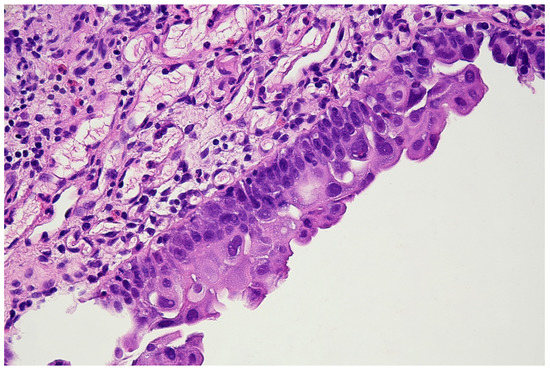

Bladder Epicheck Test: A Novel Tool to Support Urothelial Carcinoma Diagnosis in Urine Samples

Bladder cancer and upper urothelial tract carcinoma are common diseases with a high risk of recurrence, thus necessitating follow-up after initial treatment. The management of non-muscle invasive bladder carcinoma (NMIBC) after transurethral resection involves surveillance, intravesical therapy, and cytology with cystoscopy. Urinary cytology, [...] Read more.

Bladder cancer and upper urothelial tract carcinoma are common diseases with a high risk of recurrence, thus necessitating follow-up after initial treatment. The management of non-muscle invasive bladder carcinoma (NMIBC) after transurethral resection involves surveillance, intravesical therapy, and cytology with cystoscopy. Urinary cytology, cystoscopy, and radiological evaluation of the upper urinary tract are recommended during follow-up in the international urological guidelines. Cystoscopy is the standard examination for the first assessment and follow-up of NMIBC, and urine cytology is a widely used urinary test with high sensitivity for high-grade urothelial carcinoma (HGUC) and carcinoma in situ (CIS). In recent years, various urinary assays, including DNA methylation markers, have been used to detect bladder tumors. Among these, the Bladder EpiCheck test is one of the most widely used and is based on analysis of the methylation profile of urothelial cells to detect bladder neoplasms. This review assesses the importance of methylation analysis and the Bladder EpiCheck test as urinary biomarkers for diagnosing urothelial carcinomas in patients in follow-up for NMIBC, helping cytology and cystoscopy in doubtful cases. A combined approach of cytology and methylation analysis is suggested not only to diagnose HGUC, but also to predict clinical and histological recurrences. Full article